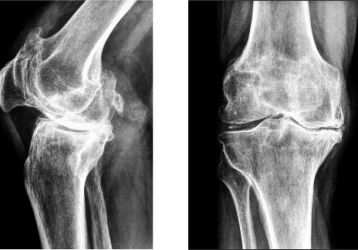

Массаж при артрозе коленного сустава: как правильно выполнять, виды, противопоказания

Как правильно выполнять массаж коленного сустава при артрозе, для чего он необходим и какие противопоказания существуют. Разновидности массажа и его эффективность.